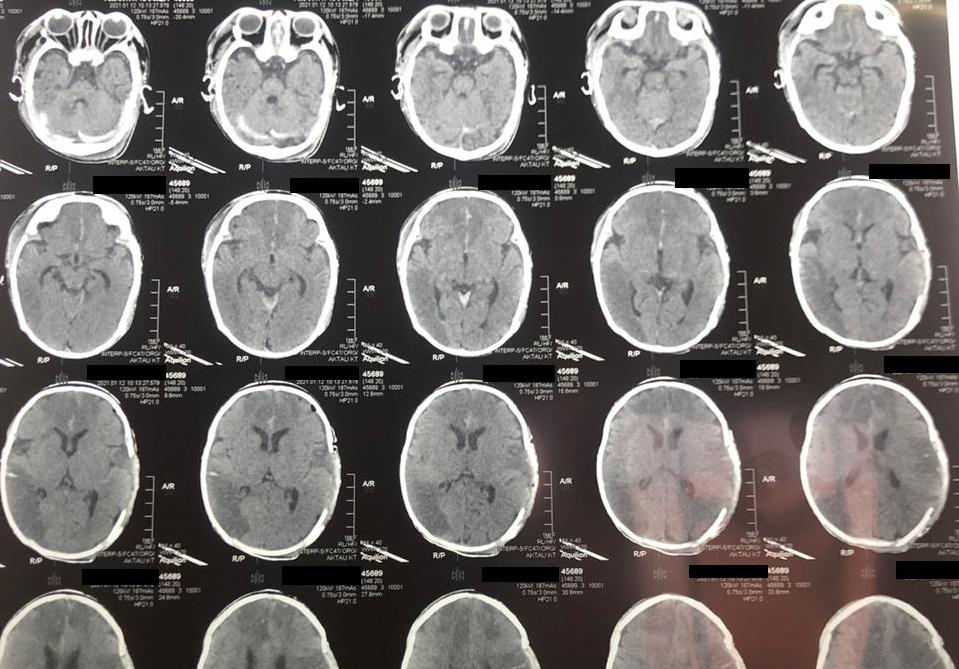

Ребенка с диагнозом «Острое нарушение мозгового кровообращения» («инсульт новорожденных» - прим. ред.) доставили в Мангистаускую областную многопрофильную детскую больницу 9 января.

У двухмесячного младенца зафиксировали отек головного мозга, дислокационный синдром и кому I-II степени. Благодаря усилиям врачей, 10 января состояние ребенка удалось стабилизировать. В экстренном порядке ему провели операцию по трепанации черепа, которая продлилась два часа.

Фото: предоставлено врачом

«Такие случаи редко заканчиваются положительным результатом, но нам удалось спасти ребенка. В настоящий момент пациента перевели в отделение травматологии, он находится в среднетяжелом состоянии», - сообщил детский нейрохирург Ербол Кенжевалов.